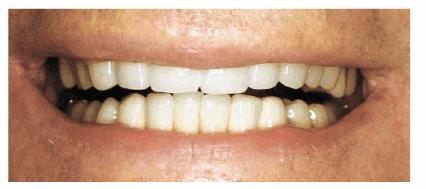

Figures 29-12A to C show a 75-year-old woman who presented

with severe root caries and moderate periodontal disease. Her daughter, who

disclosed that her mother was difficult to please, referred her. The daughter

was very supportive of her mother receiving dental treatment; however, her

mother was initially not interested. The mother did not think that the esthetic

aspect of dentistry was important. During consultation with the dentist, the

mother was informed of the infection in her mouth and the potential effect that

this could have on her future health and functionality. The patient consented

to have the maxillary arch restored with fixed prosthodontics. She refused to

accept treatment for her mandibular teeth, preferring to use her existing

partial denture. Figures 29-12D, and 29-12E show the final result after periodontal and

prosthodontic treatment. Although the patient was not particularly grateful to

have the dental treatment, her family was thrilled to have the caries infection

removed and the esthetic appearance improved. The patient lived with her

esthetically improved appearance for an additional 13 years.

Figure 29-12A to C: This 75-year-old woman had severe root caries and moderate periodontal disease.

Figure 29-12D: Although this woman stated that she would "just as soon have her teeth extracted," she was motivated to have both periodontal and prosthodontic treatment.

Figure 29-12E: The patient's smile after esthetic dental treatment shows just how much she appreciated her dental treatment.